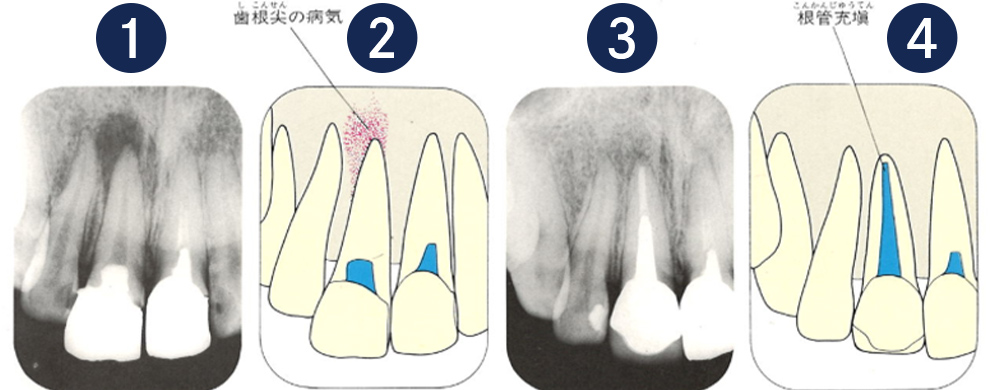

こちらのレントゲン写真を見てください。どちらかの歯医者さんで神経を取っています。根管に入れる薬は白く映ります。赤矢印部分です。一番右側が模式図ですが、青い部分が薬、根っこの先の赤点が化膿している部分です。

薬がほとんど入っていないのがわかります。黄矢印部分です。青矢印まで薬が入らないといけないのですが、全く入っていません。その結果、根っこの先が黒くなっています。膿が貯まって化膿すると黒く写ってくるのです。

別な歯科医院で治してもらいました。薬が根の先まで入っているのがわかります(黄矢印)。 根尖の黒い影が消失しています(赤矢印)。骨が再生すると白く写るようになります。

①の写真はどちらかの歯医者さんで神経を取ってもらったレントゲン写真です。根っこの中に薬が全く入っていません。

②の模式図で青く描かれている部分が薬です。

根の先を見ると小豆ぐらいの大きさの黒い影が見えます。根の中でばい菌が繫殖し感染を起こすとこのような黒い影ができます。黒い影の部分は膿(ウミ)が貯まっています。こうなると腫れて痛みが出てくるのです。

③、④の写真はそれを治した後のレントゲン写真とその模式図です。白く映っている薬が根の先まできちんと入っているのが確認できます。そして根の先にあった黒い影が消えているのが分かります。根の先の炎症が治って、骨が再生すると白く映るのです。

実はこのケース、歯医者さんの神経を取る治療でこのような根っこの病気になってしまったのです。そこでこの患者さんは神経を取った歯医者さんではなく、別の歯医者さんに受診して、根っこの治療をして治したのです。